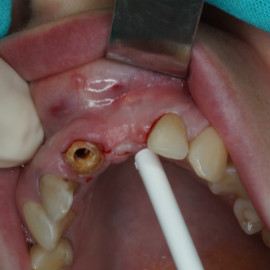

Odbudowa kości, dziąsła, implantacja, korony protetyczne, dwa prawe dolne trzonowce.

Pacjentka lat 72, od kilkudziesięciu lat chorująca na cukrzyce I typu, obecnie od 10 lat na pompie insulinowej. Profesor medycyny, siostrzenica pacjentki prowadzi swoją ciocię diabetologicznie, pacjentka świadoma zagrożeń przy zabiegach regeneracji kości i implantacji w takim ogólnym stanie zdrowia. Po rekonstrukcji tkanek miękkich i kości osadzono dwa implanty o średnicy 5,0 mm. Na zdjęciu śródzabiegowym widać zadowalające wyniki rekonstrukcji tkanki kostnej. Po upływie kilku miesięcy wykonano nadbudowę protetyczną.